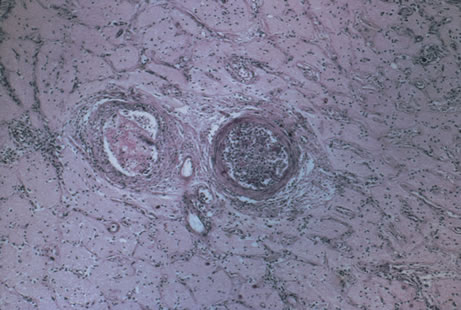

Any cell type may be infected, appearing larger than normal (cytomegalic) and demonstrating eosinophilic intranuclear “owl's eye” and smaller intracytoplasmic viral inclusion bodies, which are better seen with Giemsa or Papanicolaou's stains (Fig. 8). Histologic examination of tissue specimens, including bronchoalveolar lavage fluid and urine, may be useful for diagnosis.